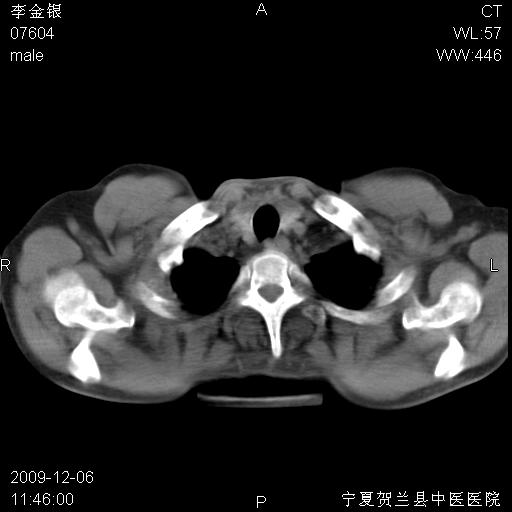

该病人 ,男,62岁,主因咳痰带血两天

支气管壁明显增厚 管腔狭窄,腔静脉后多个淋巴肿大,结合年龄病史考虑右肺上叶中央型肺癌并阻塞性肺炎